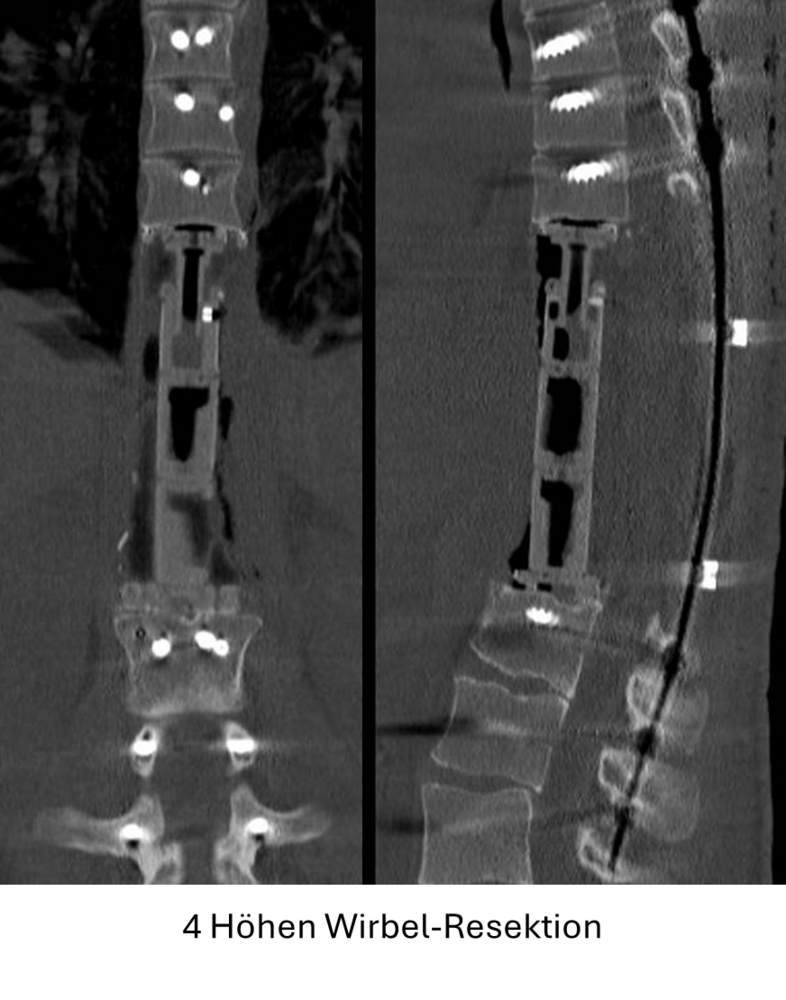

- Schmerzstillende stabilisierende Maßnahmen und Versteifungsoperationen bei primärem sowie sekundären Wirbelsäulentumoren (Metastasen)

Seit 2017 führen wir unsere Stabilisierungs- und Versteifungsoperationen mit einem intraoperativen CT (s.o. AIRO©, Fa. Brainlab) durch. Diese intraoperative Computertomographie liefert direkt im Operationssaal während des Eingriffs hochauflösende Bilder von der Wirbelsäule. Zusammen mit einer Navigationssoftware wird ein dreidimensionaler Plan der entsprechenden Körperregion erzeugt. Mit Hilfe der Bildgebung können wir die notwendigen OP-Schritte plangerecht umsetzen und z.B. Implantate mit sehr hoher Präzision einsetzen. Gerade bei komplizierten Eingriffen an der Wirbelsäule hilft die neue OP-Technik, Patienten sicher und schonend zu therapieren. Die intraoperative Bildgebung, direkt im OP, erlaubt komplexe Operationen genauer und sicherer durchzuführen und dem Operateur noch während der Operation das Ergebnis zu überprüfen und bei Bedarf zu optimieren. Belastende Folgeoperationen sind so deutlich seltener und die Behandlungsqualität und Sicherheit für Patienten dadurch erheblich verbessert.